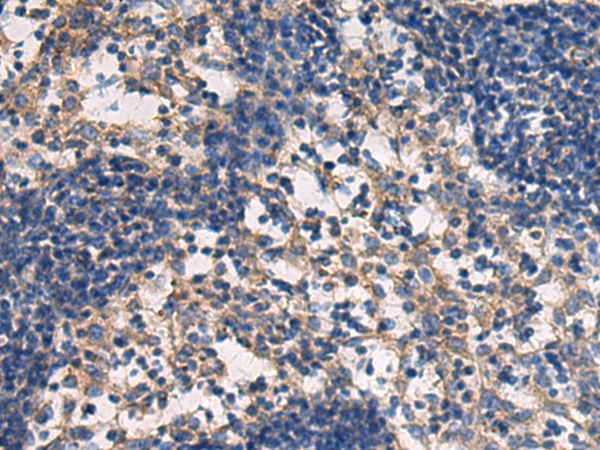

分类: 科研抗体货号: P06441别名: PC; APC; PROC1; THPH3; THPH4应用: WB,IHC反应种属: Human